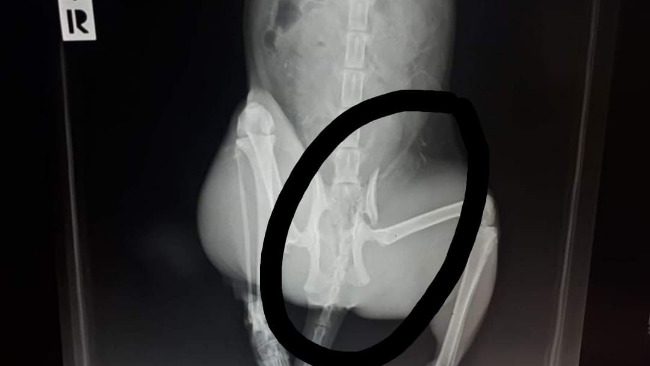

Zdjęcie RTG, widoczne złamanie z przemieszczeniem.

Czarna to kotka niczyja. Żyje na ulicy, dokarmiana przez Panią Halinę. Dwa miesiące temu została wysterylizowana. Jest młodziutka, ma nie więcej niż 1,5 roku. Wczoraj Czarna została znaleziona na ulicy, jak próbowała się czołgać w kierunku swojej budki. Bardzo boleśnie miauczała. Została zawieziona do kliniki, gdzie okazało się, że ma połamaną miednicę, prawdopodobnie w wyniku potrącenia przez samochód. Koniecznie trzeba operować, ponieważ inaczej kotka zostanie kaleką niezdolną do samodzielnej egzystencji. Alternatywą dla operacji jest eutanazja. Kotka może odzyskać sprawność, ale koszt samej operacji to ponad 700 zł, nie mówiąc o opiece okołooperacyjnej. Proszę bardzo o pomoc kotce. Jej karmicielka nie jest w stanie ponosić takich kosztów, zwłaszcza, że ma pod opieką kilkadziesiąt kotów. Nie zostawiamy Czarnej bez pomocy. Proszę.

EDIT. 21.08. Odbyła się operacja Czarnej. Miednica została poskładana. Lekarz, która operowała kotkę powiedziała, że bez operacji kości nie miały szansy zrosnąć się prawidłowo - byłoby wskazanie do eutanazji, bo kotka nie mogłaby się poruszać ani samodzielnie wypróżniać. Teraz kotka będzie przez 2 miesiące wracać do zdrowia, a my musimy zapłacić fakturę za operację i leczenie. Jak tylko kotka wyjdzie ze szpitala i dostaniemy fakturę natychmiast ją umieszczę.